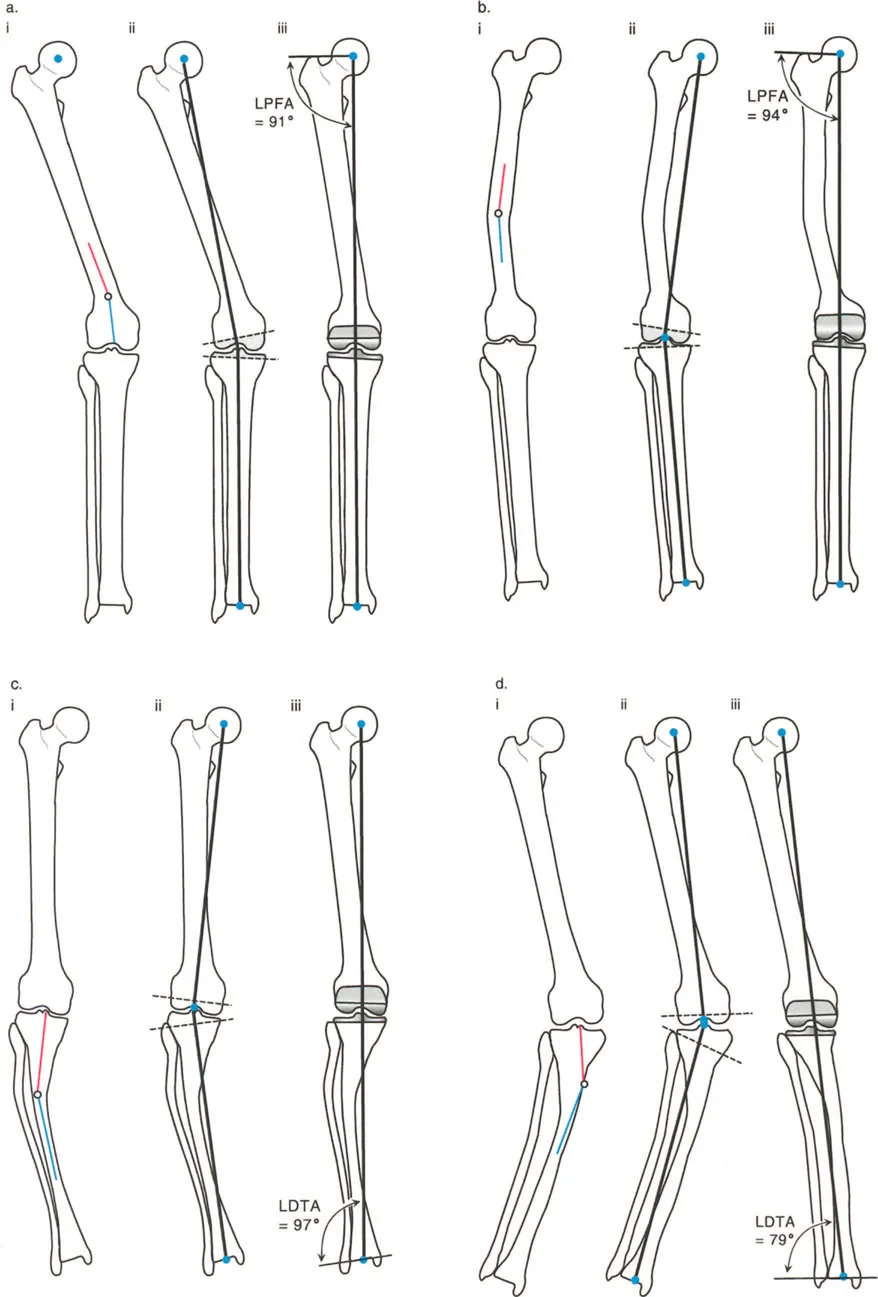

أمثلة أخرى رئيسية للتشوهات الديناميكية تشمل "الورم الفخذي المفرط" (Severe Femoral Anteversion) و "الورك الأفحج" (Coxa Vara). في كلتا هاتين الشذوذات المعمارية، يتم تقصير الطول الفيزيائي لذراع الرافعة لعضلات المبعدة (Abductor muscles) بشكل مرضي بسبب التشوه العظمي نفسه. قد تكون عضلة الألوية الوسطى (Gluteus Medius) صحية تمامًا، ومعصبة جيدًا، وقادرة على توليد قوة بيولوجية طبيعية، لكنها تعاني من خلل وظيفي سريري عميق لأن ميزتها الميكانيكية قد سُلبت بسبب الهندسة الهيكلية المتغيرة. هذه الفئة الفرعية المحددة من الأمراض تُعرف باسم "تشوه في طول ذراع الرافعة".

صاغ مصطلح "خلل وظيفة الذراع الرافعة" (Lever Arm Dysfunction) لأول مرة من قبل غيج (Gage) في عام 1991 لوصف التشوهات العظمية المعقدة التي تنشأ لدى الأطفال المتنقلين المصابين بالشلل الدماغي. ومع ذلك، يمتد تطبيقه إلى ما هو أبعد من جراحة الأعصاب والعظام لدى الأطفال ليشمل الممارسة اليومية لجراحي الإصابات وإعادة بناء العظام لدى البالغين.

بشكل خاص، يصف خلل وظيفة الذراع الرافعة حالة سريرية تتشوه فيها أذرع الرافعة الداخلية و/أو الخارجية بسبب سوء محاذاة العظام، أو التشوهات الالتوائية، أو تيبسات المفاصل الموضعية.

- الورك الأفحج (Coxa Vara): تشوه خلقي أو تطوري في عظم الفخذ يؤدي إلى تقصير ذراع الرافعة لعضلات الورك المبعدة، مما يضعف قدرتها على تثبيت الحوض.

- الورم الفخذي المفرط (Femoral Anteversion): دوران مفرط لعظم الفخذ نحو الداخل، يؤثر على توجيه المفصل ويغير كفاءة عمل العضلات.

- أشعة الأطراف الطويلة (Long Leg Films): تُؤخذ هذه الأشعة من الورك إلى الكاحل في صورة واحدة لتقييم المحور الميكانيكي الكامل للطرف السفلي وتحديد أي انحرافات.

- التصوير المقطعي المحوسب (CT Scans): يوفر صورًا ثلاثية الأبعاد للعظام، وهو مفيد بشكل خاص لتقييم التشوهات الالتوائية (مثل الورم الفخذي المفرط) وتحديد موقع مركز دوران الانحراف (CORA) بدقة.